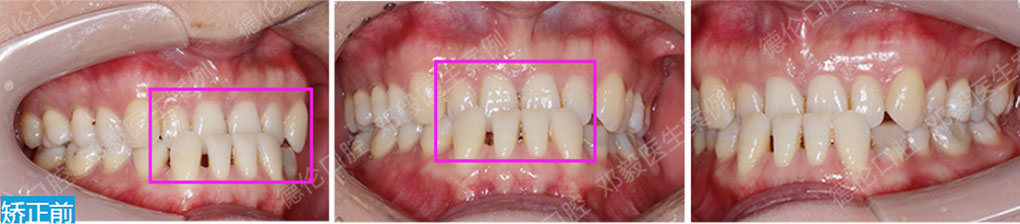

- 【診斷】

先天缺少下切牙2顆

上前牙錯(cuò)位于下前牙后側(cè),前牙無咬合功能,上牙槽及上唇后縮

打造醫(yī)生:德倫口腔正畸中心鄧毅醫(yī)生

- 【治療方案】

調(diào)整弓形及配合Ⅲ類牽引,實(shí)現(xiàn)頜跳躍

矯治前后對(duì)比

牙列整平排齊,前牙內(nèi)收;覆蓋、覆合正常;尖牙和磨牙達(dá)到中性關(guān)系;上下中線對(duì)齊;下頜后縮改善